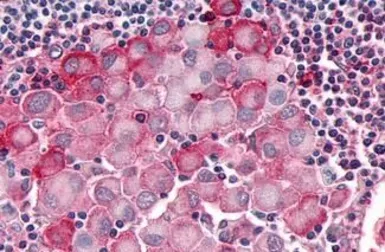

OR10R2 antibody

Cat. No. GTX71527

ApplicationsIHC-P

ReactivityHuman, Rabbit, Bovine, Monkey